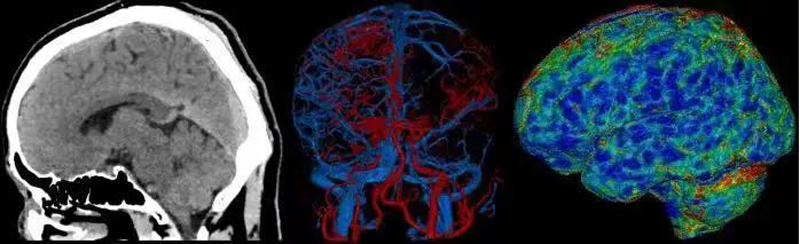

4D一站式卒中检查

天河640可实现单圈扫描的全脑覆盖成像。采用宽体采集进行头部平扫、动态CTA及CTP成像,一次检查即可获得全脑平扫图像、动静脉造影图像和灌注图像。结合集成脑灌注分析、4D动静脉动态评估等高级后处理手段,不仅可应用于急诊缺血性脑卒中的影像评估,还可助力脑血管畸形、脑动脉瘤等其他脑血管病的结构和功能评估。